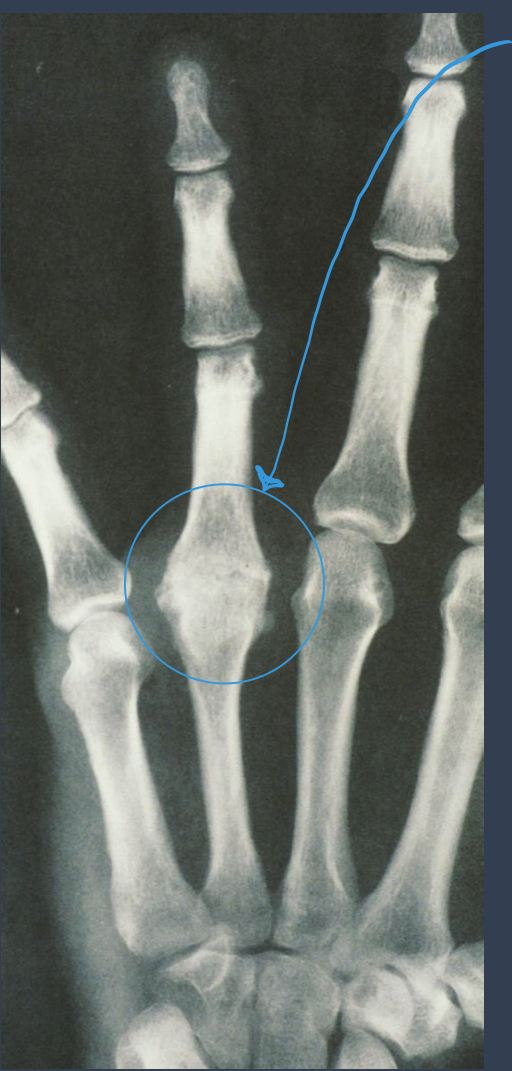

what do you think this is?

septic arthritis

NOTE: upper extremity is uncommon

what is noted here?